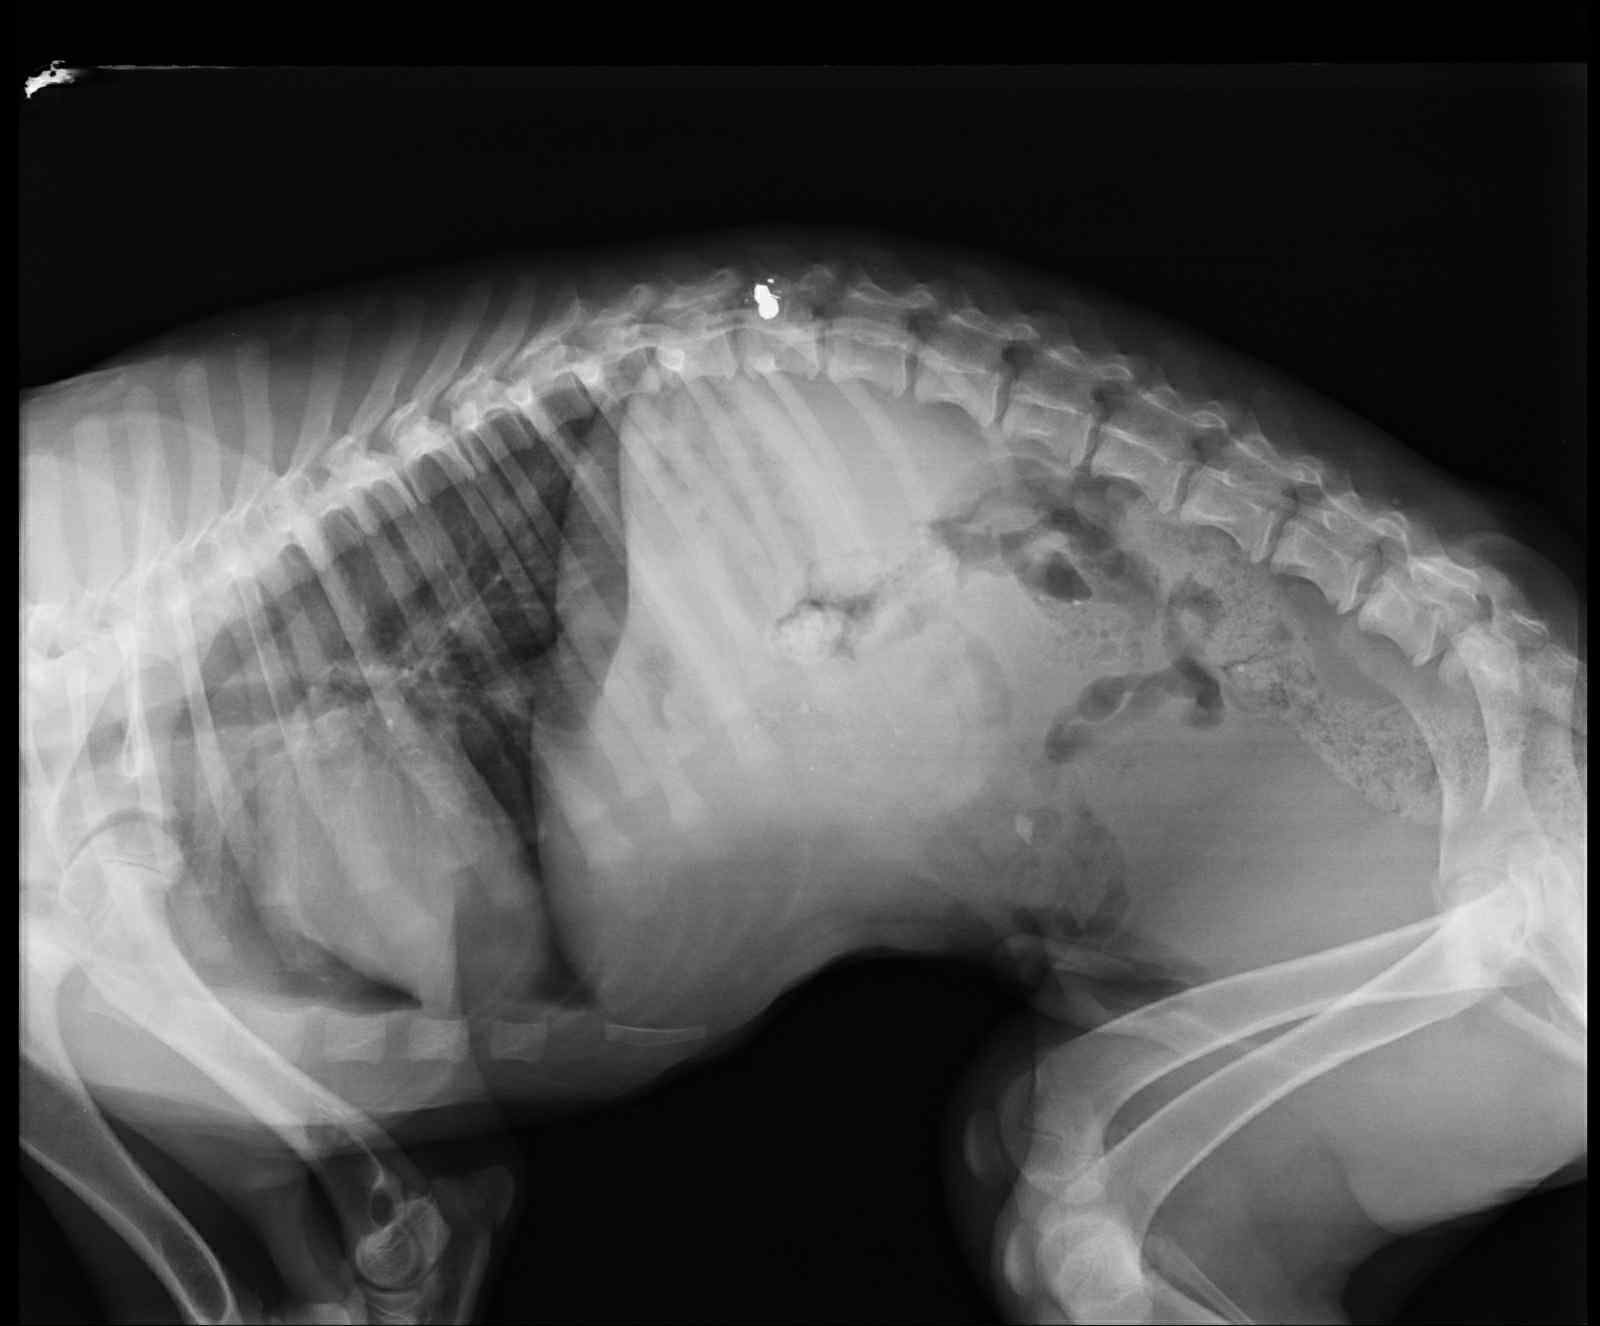

Paris war gerade einmal wenige Monate alt, als sein Besitzer sein Leben auf grausame Weise beenden wollte. Kalt und ohne Mitgefühl richtete er ein Gewehr auf das unschuldige Hundekind und schoss. Paris überlebte – schwer verletzt schleppte er sich durch die Berge. Wir können uns kaum vorstellen, was der kleine Knirps für Schmerzen hatte und wie verloren er sich in diesem Moment gefühlt haben muss. Am Ende wurde er von einem Kind gefunden und ins städtische Tierheim von Alexandria gebracht. Doch selbst für gesunde Hunde ist dieser Ort kaum ein Hoffnungsschimmer. Für Paris, der durch das Erlebte querschnittsgelähmt ist, hätte dies vermutlich einen langsamen und qualvollen Tod bedeutet. Zwischenzeitlich nahmen ihn daher griechische Tierschützer auf – doch auch das war nur eine Übergangslösung für ihn.